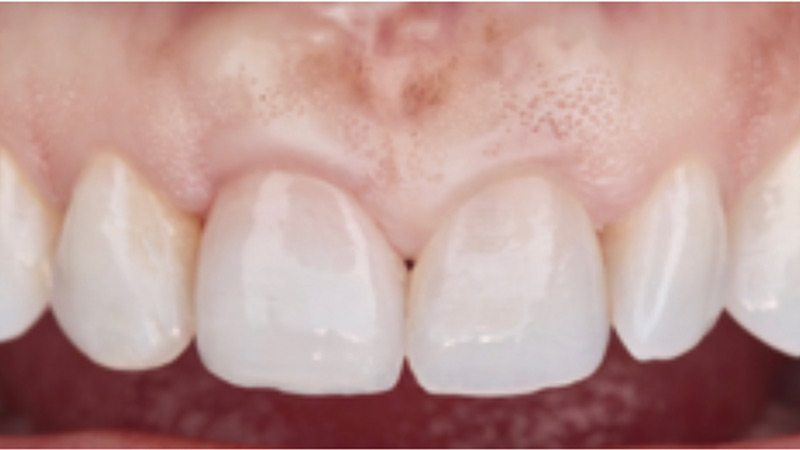

Minimally Invasive Surgical And Prosthetic Management Of A Failed Implant In The Esthetic Zone

Said-fig-18B2 alternate text for this image

Introduction Management of the peri-implant soft tissue contours is a critical component of esthetic implant therapy. In patients with high esthetic demands, minimally invasive surgical techniques and prosthetic soft tissue development are important in achieving a seamless, naturally appearing implant supported restoration. Prosthetic tissue conditioning and accurate translation of the restorative contours to the final … Read more